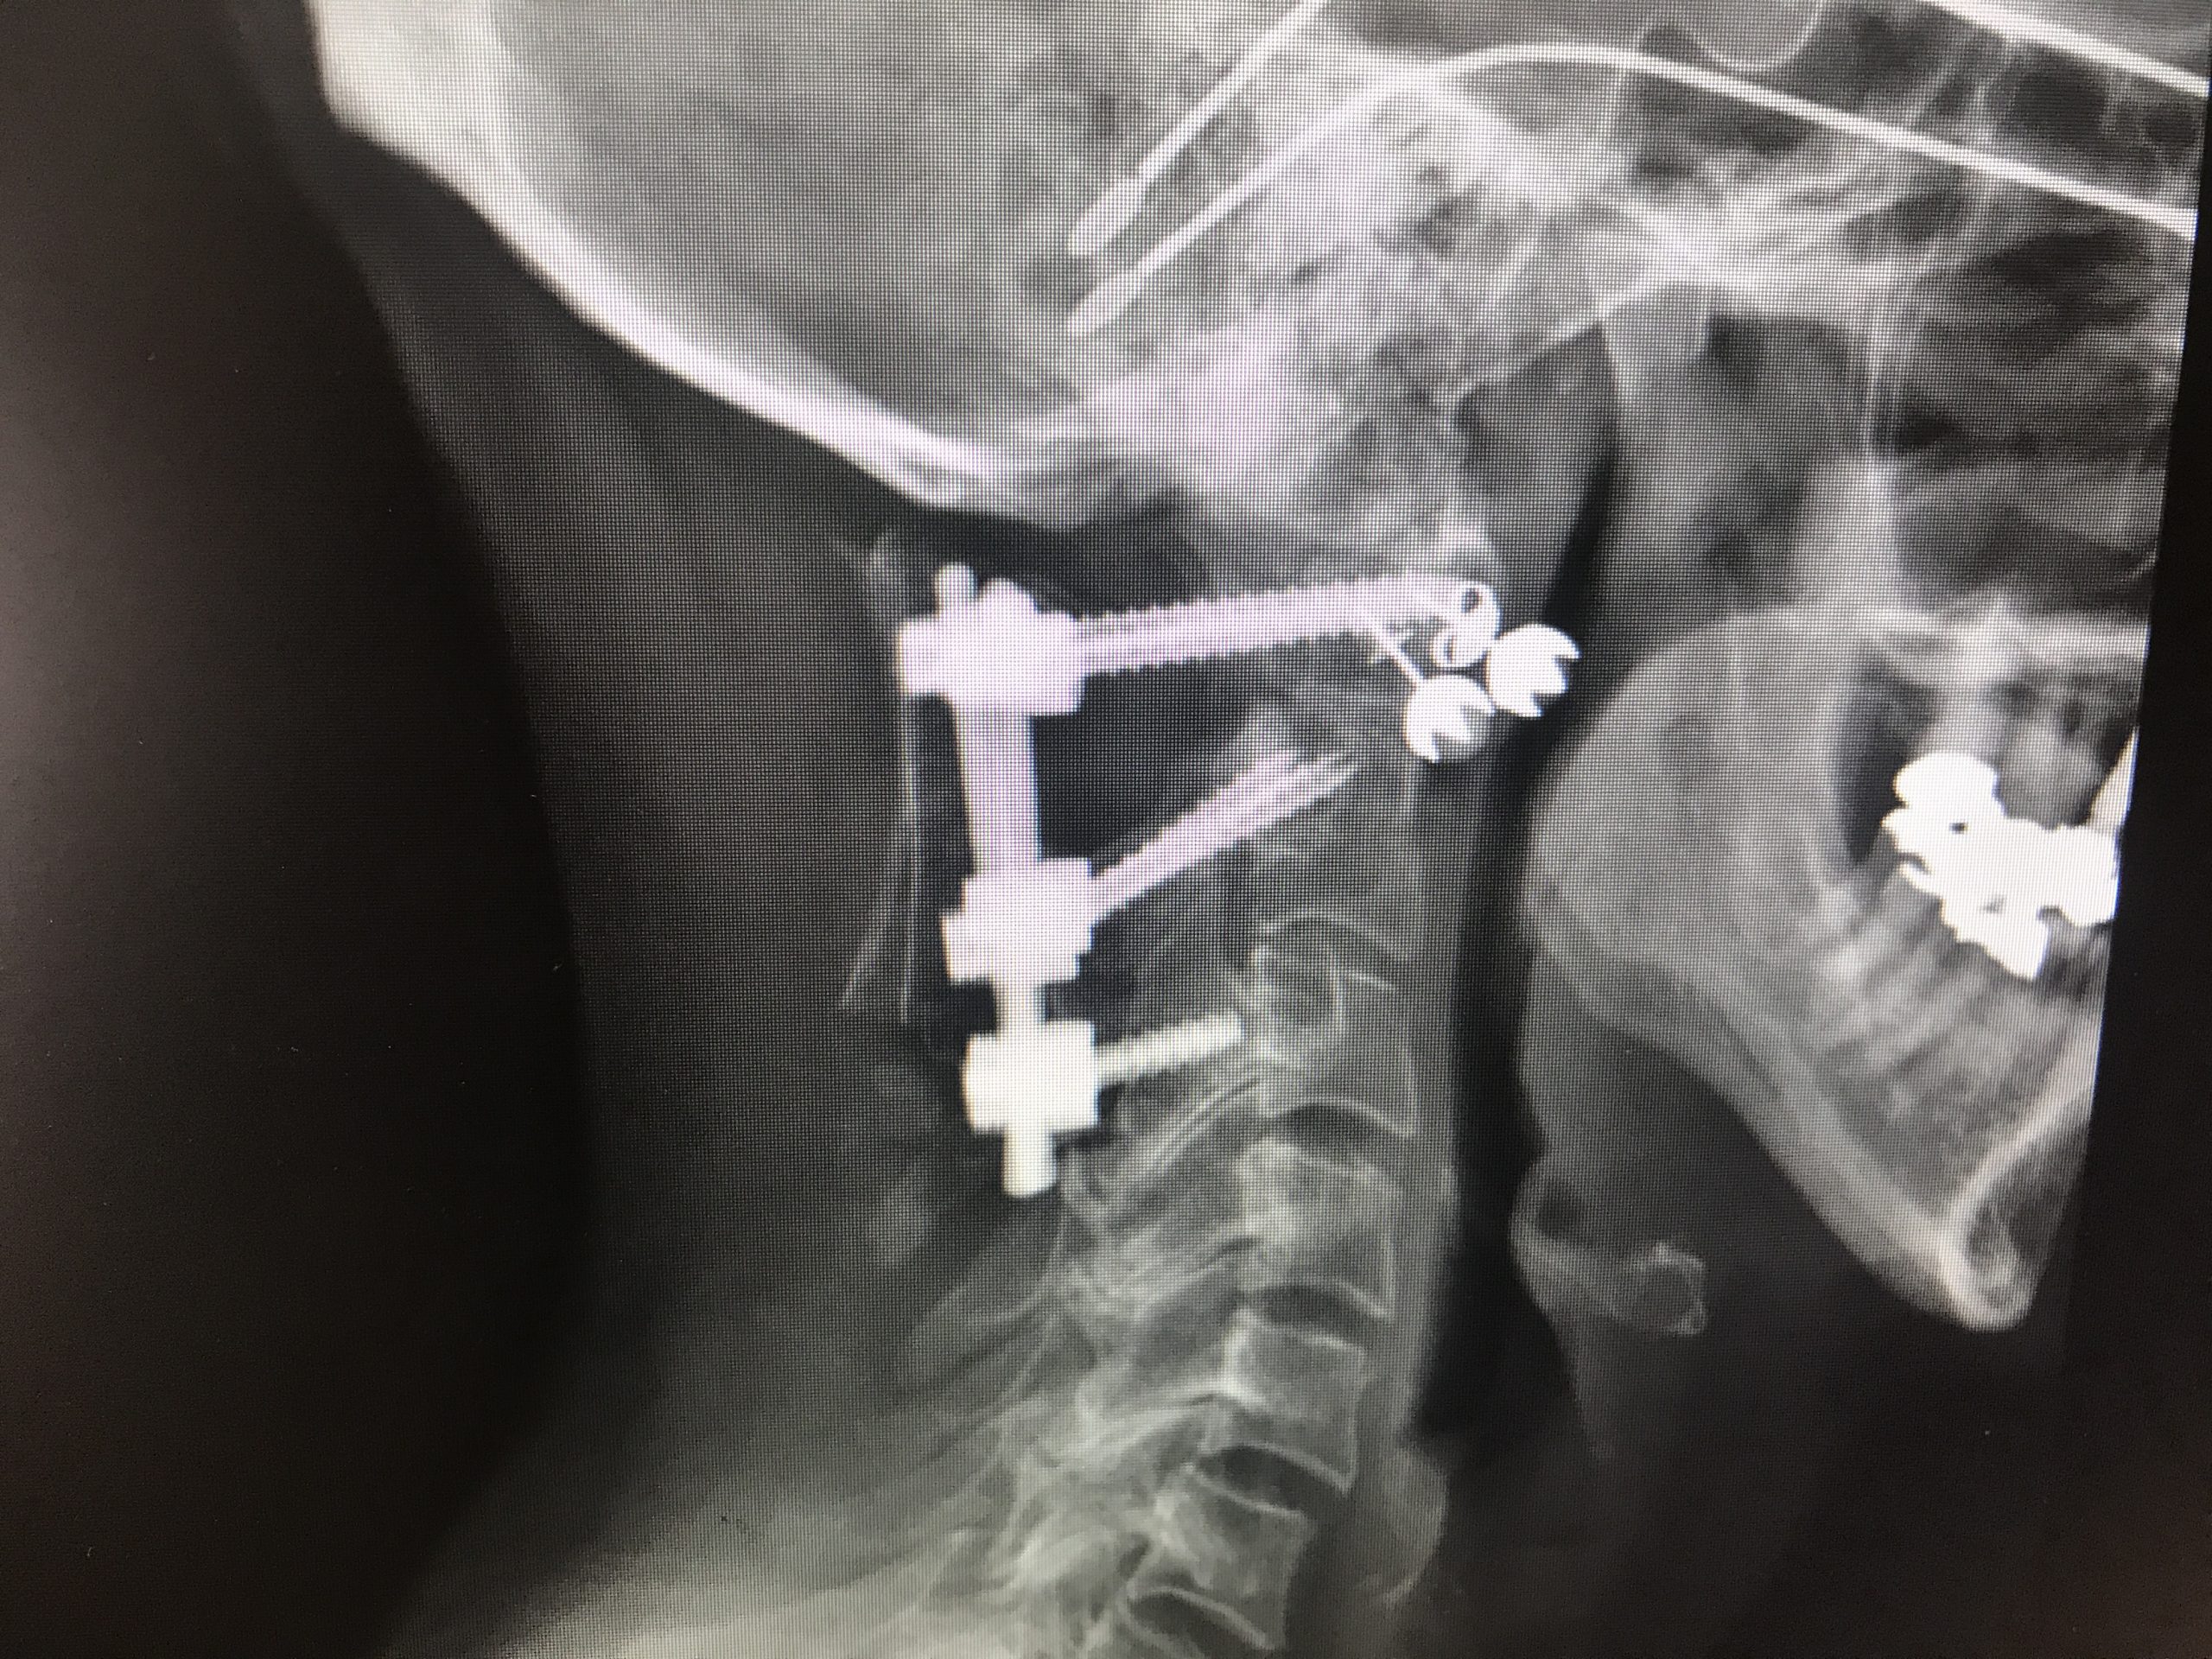

After shattering my C2 vertebra in a wreck several years ago, my C1 to C3 were bolted together and bone grafted into one chunk of bone. The following months of physical therapy were a process of vestibular retraining, getting the inner ear to take up the balance slack. I walked with a cane and wore a neck brace if I was somewhere I might fall.

Before the cervical fusion operation, the lead surgeon and his medical residents came into my hospital room. The doctor explained they were going to bolt the shattered remnants of my C2 like sandwich meat between C1 and C3. Because the C1 and C2 would no longer pivot, I’d never be able to turn my head or look up or down again.